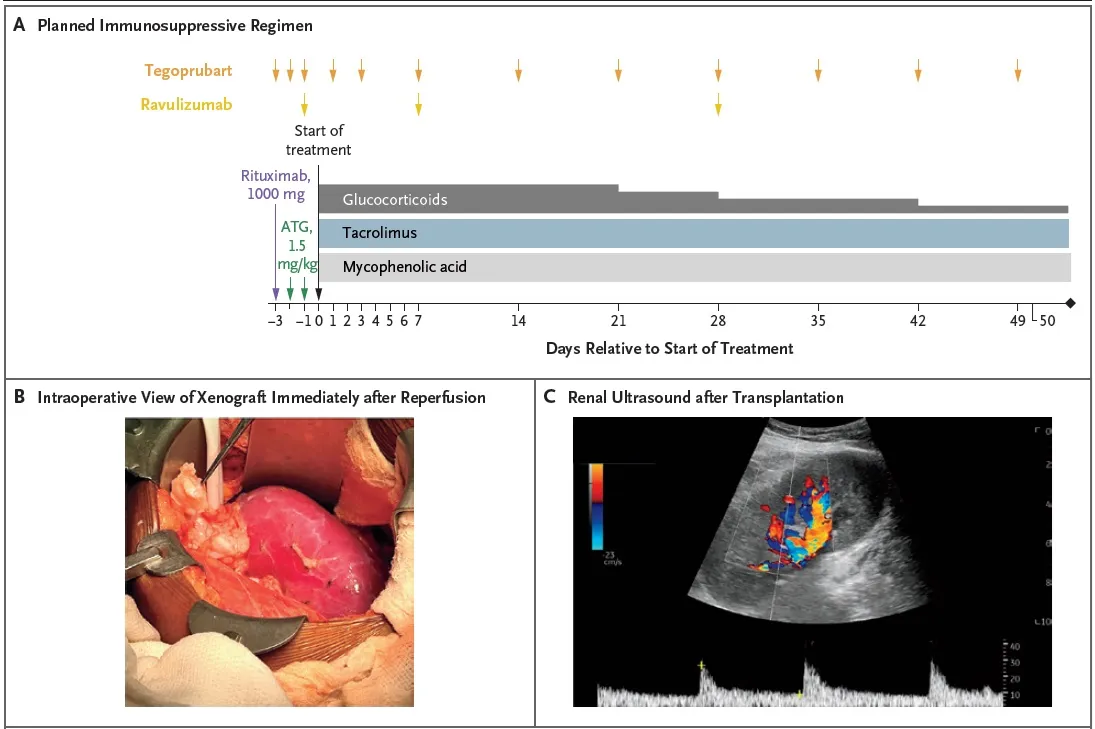

##### Imunossupressão utilizada

Indução

* Timoglobulina (ATG) 1,5 mg/kg

* Rituximabe (1000 mg)

* Tegoprubart (anti-CD154, bloqueia a produção de anticorpos)

* Ravalizumabe (anti-C5)

Manutenção

* Prednisona, tacrolimo e micofenolato

Tempo de isquemia fria: 4 horas e 38 minutos

Confere o esquema de imunossupressão utilizado, bem como achados do intraoperatório: